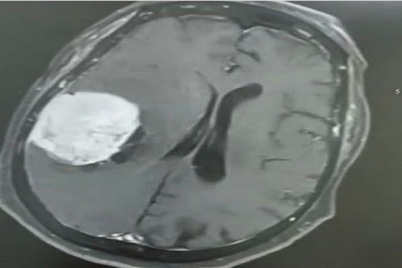

نجح فريق طبي بمستشفى الملك خالد ، أحد مكونات تجمع تبوك الصحي، في إنقاذ حياة مريضة في العقد الثامن من...

متابعات - عماد فؤاد أسهم التدخل السريع ضمن نظام مسار الرعاية العاجلة – أحد مسارات نموذج الرعاية الصحية السعودي،...